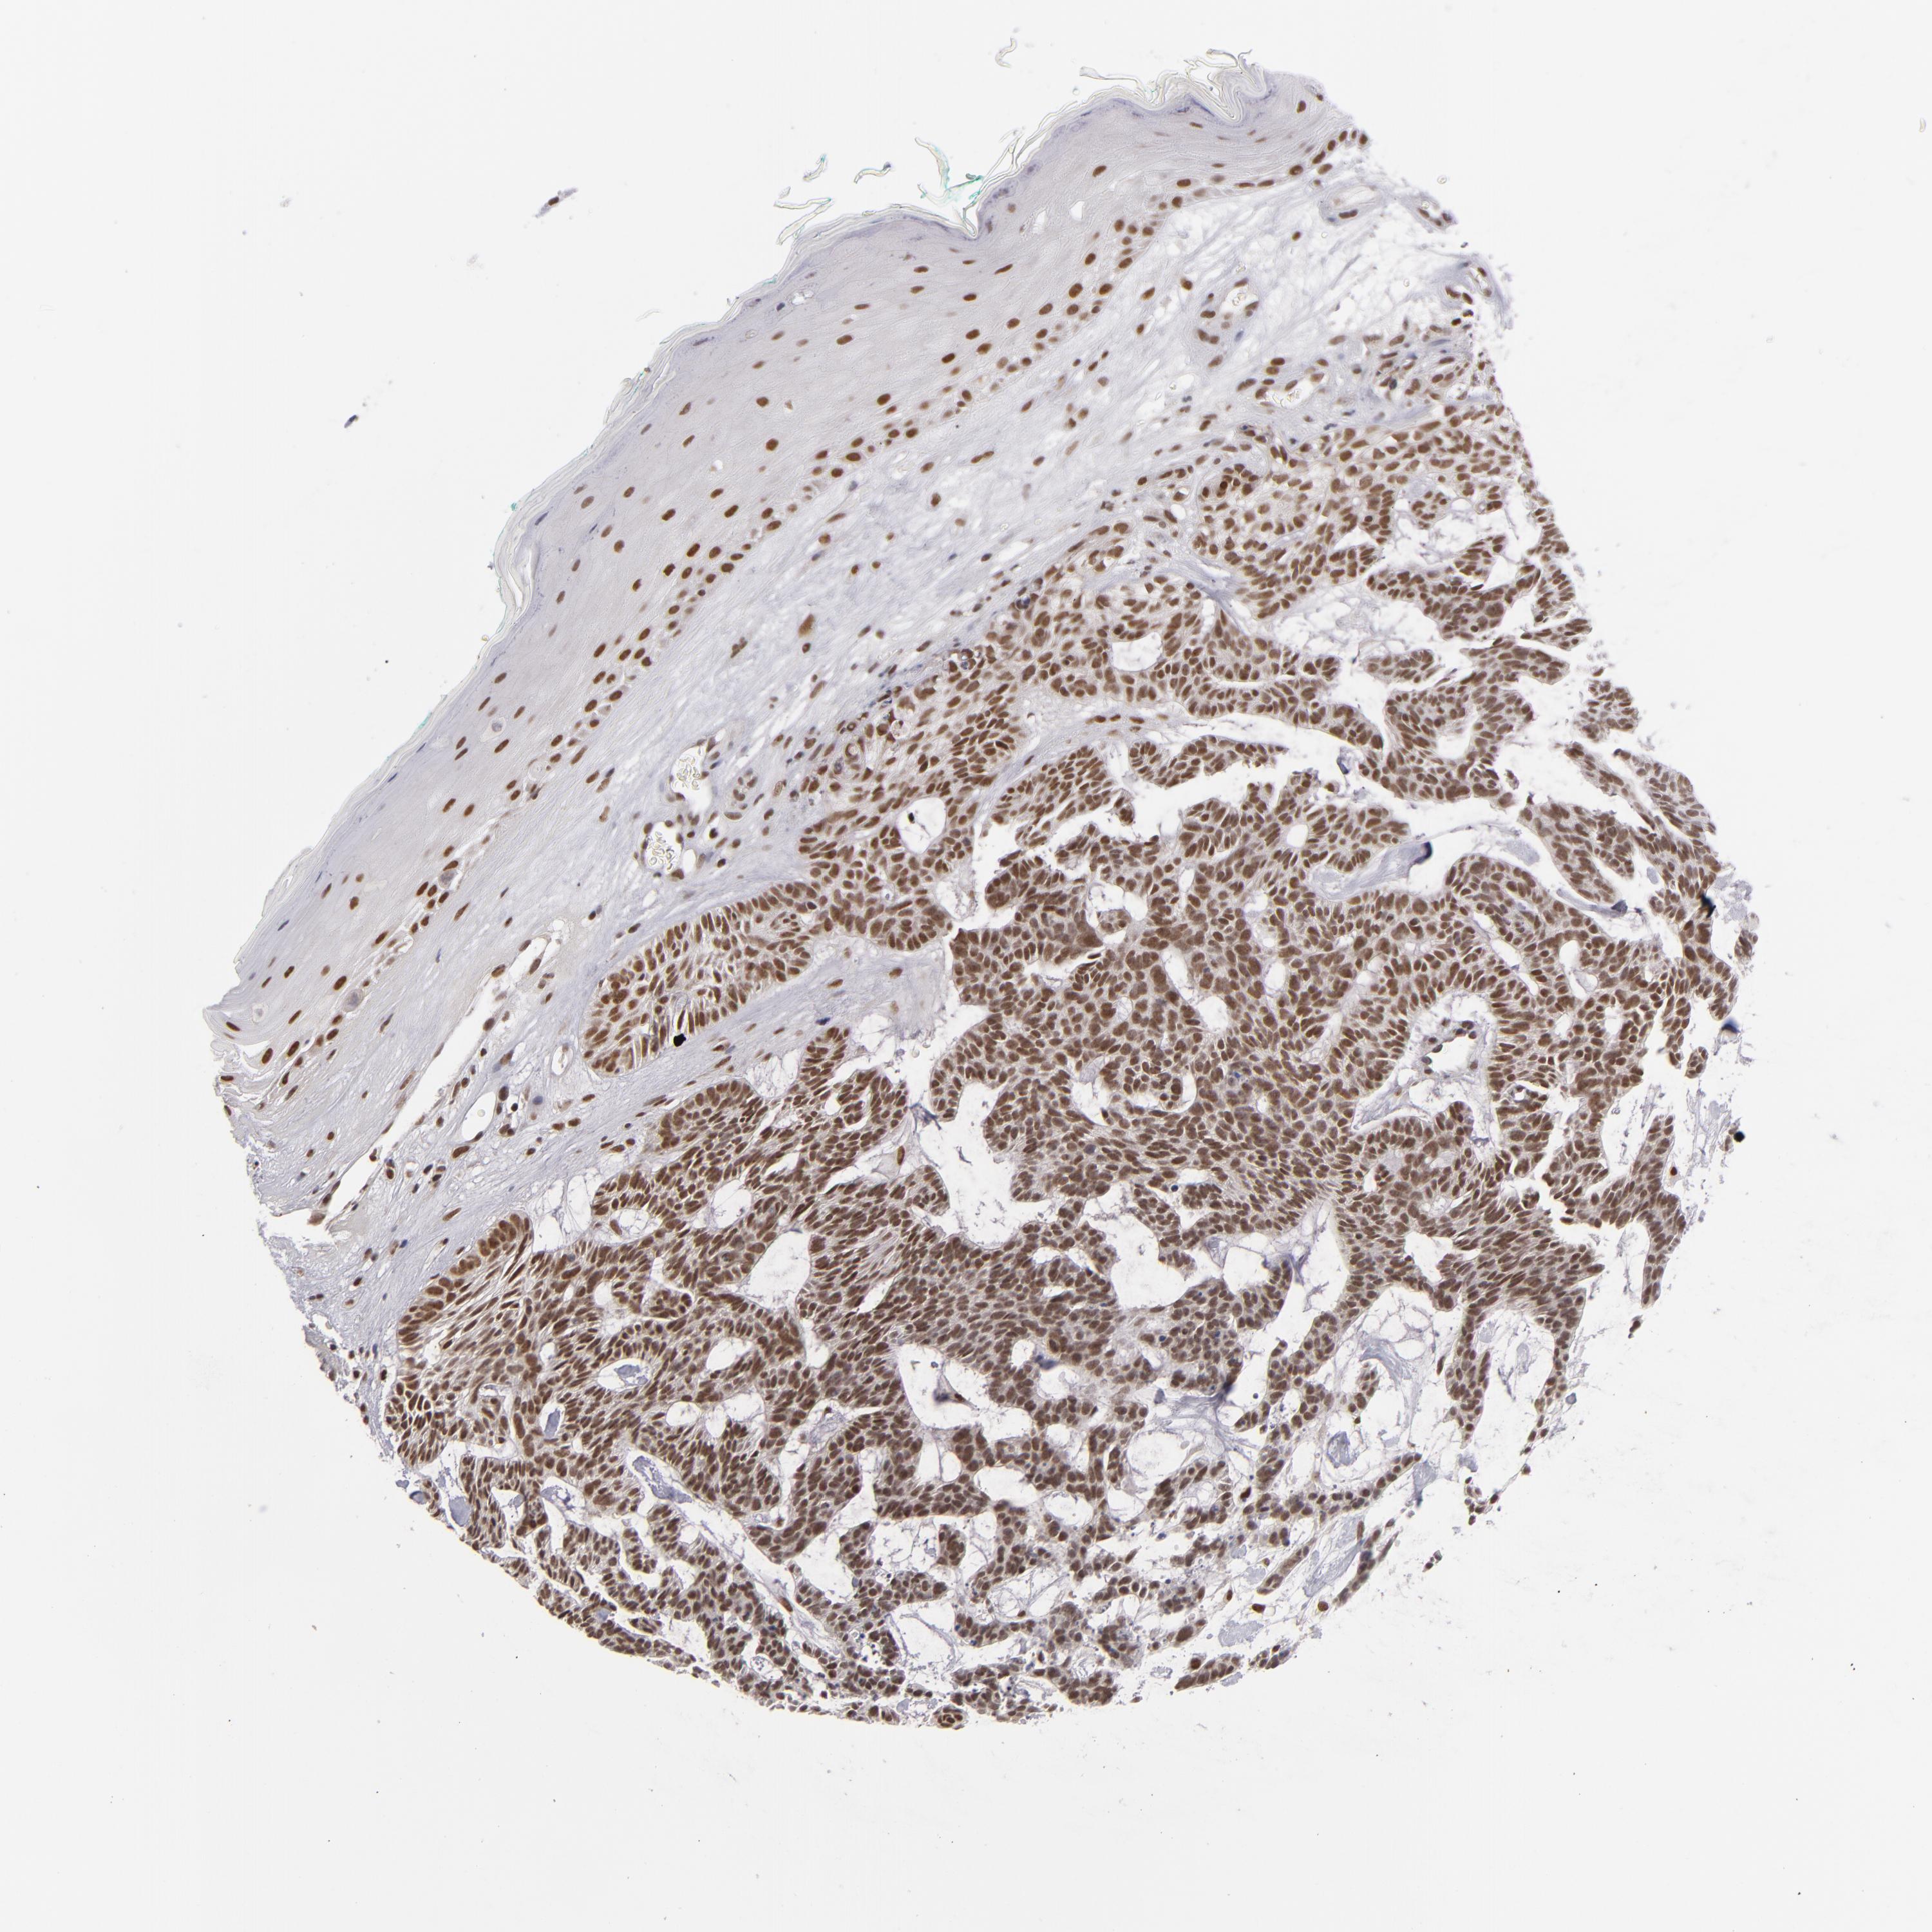

CANCER SKIN CANCER Show tissue menu

Basal cell and squamous cell cancer

SKIN CANCER - Protein expressioni

A mouse-over function shows sample information and annotation data. Click on an image to view it in a full screen mode. Samples can be filtered based on level of antibody staining by selecting one or several of the following categories: high, medium, low and not detected. The assay and annotation is described here.

Each image is clickable and will lead to virtual microscopy that enables deeper exploration of all samples and also displays staining intensity scores, fraction scores and subcellular localization as well as patient and tissue information for each sample.

Antibody HPA001824

Staining

High

Intensity

Strong

Quantity

>75%

Location

Nuclear

Squamous cell carcinoma, NOS

Basal cell carcinoma